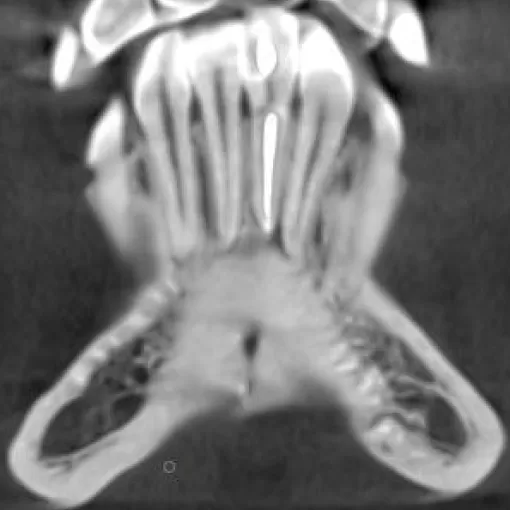

Пациент обратился с целью имплантации в области отсутствующего зуба 4.6. Однако после КЛКТ (3Д) исследования был обнаружен воспалительный процесс (киста) в области соседнего зуба 4.7 (рис. 1).